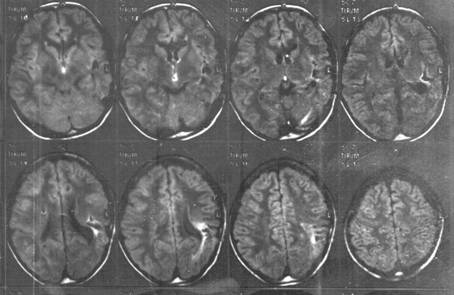

Мал. 1. МР-томографія головного мозку при епілепсії "їжі" - кіста і склерозування внутрішніх структур лівих скроневої і тім'яної часткою.